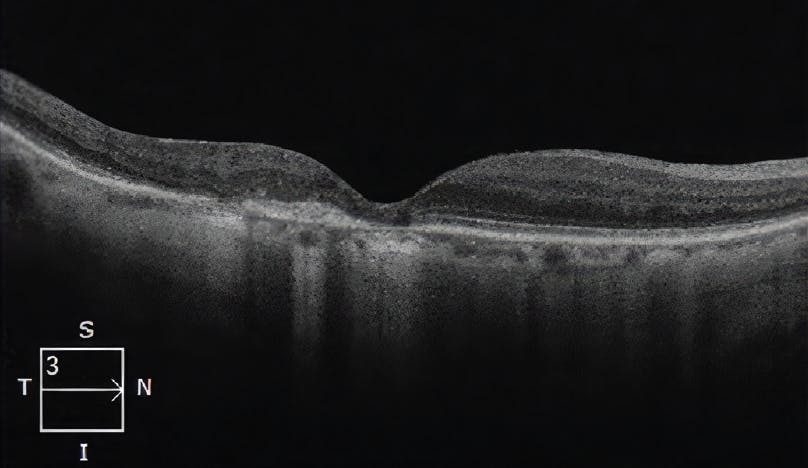

<p><strong>Figure 4. SD-OCT findings 3 months after PDT with VISUDYNE.</strong> SD-OCT shows fully resolved edema and no cysts.</p>

Figure 4. SD-OCT findings 3 months after PDT with VISUDYNE. SD-OCT shows fully resolved edema and no cysts.

One month after PDT with VISUDYNE, SD-OCT demonstrated that the patient’s macular edema and intraretinal cysts had begun to resolve (Figure 3A). FA revealed a marked decrease in vascular leakage, which was most noticeable in the superior aspect of the macula (Figure 3B). Despite improving retinal anatomy, the patient’s visual acuity had worsened to 20/80. However, 3 months after combining PDT with VISUDYNE, SD-OCT demonstrated complete resolution of macular edema and cystic changes with improvement of the RPED (Figure 4), and the patient’s visual acuity had improved from 20/80 to 20/30. Vision has been stable for 3.5 years with intravitreal injections now limited to every 3 months.